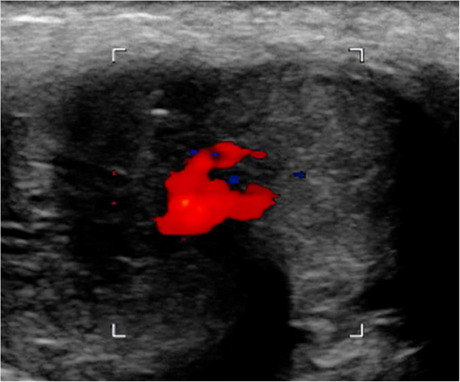

A healthy 24-year-old male patient presented with a history of straddle-trauma from a bicycle accident and concomitant non-ischemic-priapism lasting for ten days. On a contrast-enhanced computed tomography scan an arterio-cavernous fistula establishing a connection between the right cavernosal artery and the ipsilateral corpus cavernosum was diagnosed. Super-selective unilateral arterial embolization was performed using gelatin sponge and microcoils. Technical success became evident with the consecutive detumescence of the penis and long-term preservation of baseline urogenital functions.

一位24岁的健康男性患者,有自行车事故造成的跨骑创伤史,并伴有持续10天的非缺血性阴茎勃起。在对比增强的计算机断层扫描上,诊断出动脉-海绵体瘘,建立了右海绵体动脉和同侧海绵体之间的连接。采用明胶海绵和微线圈对单侧动脉进行超选择性栓塞。技术上的成功是显而易见的,阴茎的连续消肿和长期保存基线泌尿生殖功能。